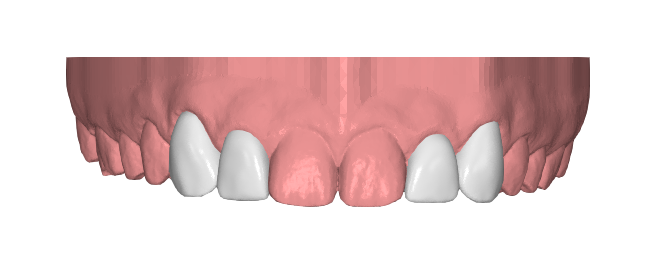

Desde Elevantia Solutions propusimos un Injectable Composite Design con carillas únicamente en esas piezas, para cerrar los espacios sin necesidad de limar sus dientes. Se trabajaron varias versiones del diseño hasta conseguir un resultado totalmente adaptado a sus expectativas, respetando al máximo la estructura dental natural al cerrar los espacios